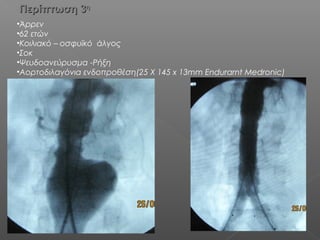

Περίπτωση 3Περίπτωση 3ηη

•Άρρεν

•62 ετών

•Κοιλιακό – οσφυϊκό άλγος

•Σοκ

•Ψευδοανεύρυσμα -Ρήξη

•Αορτοδιλαγόνια ενδοπροθέση(25 X 145 x 13mm Endurarnt Medronic)